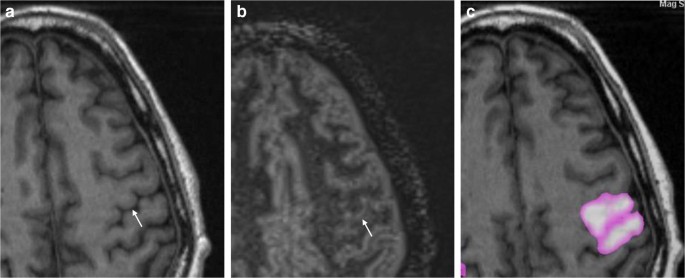

Spot And Diffuse Signs Quantitative Markers Of Intracranial Hematoma Expansion At Dual Energy Ct Radiology Által nyújtott indavideo.hu szolgáltatás felhasználási feltételeit és a szolgáltató adatvédelmi tájékoztatóját elolvastam, megértettem, és hozzájárulok ahhoz.